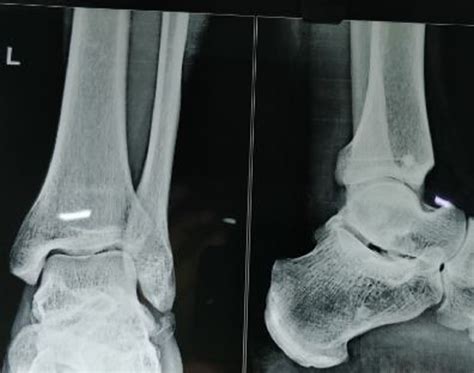

• Imaging Tests: Imaging tests, such as X-rays, MRI, or CT scans, are used to visualize the bone and cartilage within the ankle joint. These tests can help identify the location and extent of the lesion.

Imaging tests are particularly important in diagnosing Osteochondritis Dissecans Ankle, as they can provide detailed information about the condition of the bone and cartilage.